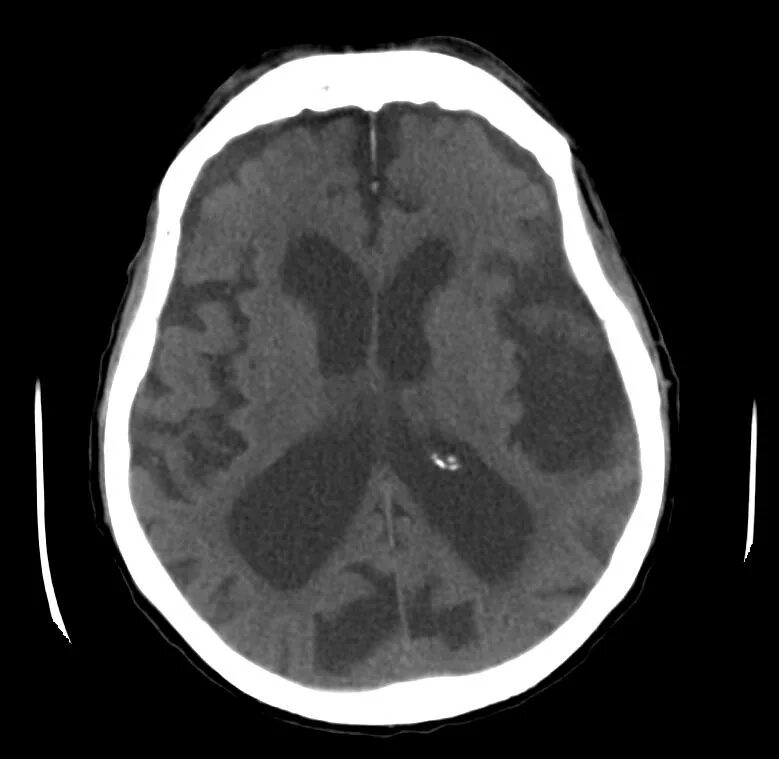

Диффузно атрофические изменения головного